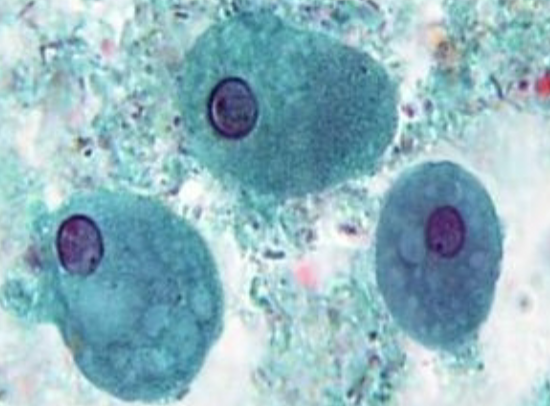

Entamoeba histolytica (cyst) >10

Entamoeba histolytica (cyst)

Entamoeba histolytica (cyst)